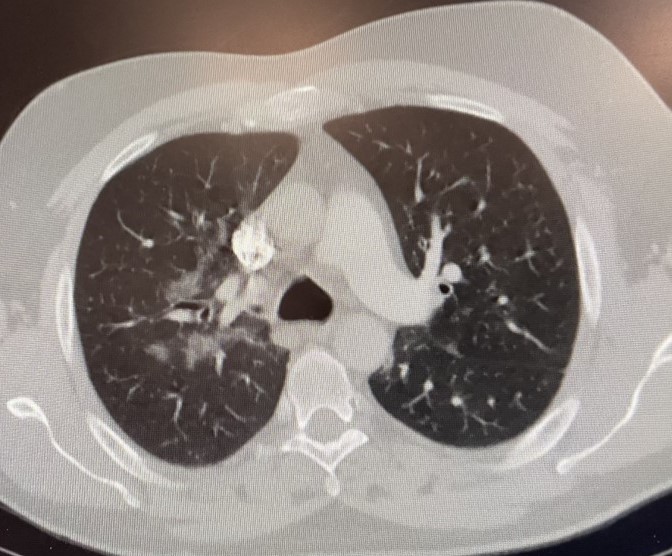

A PA of the chest shows RLL infiltrates (left image). A CT scan of the chest confirms the presence of RLL infiltrates (right image).